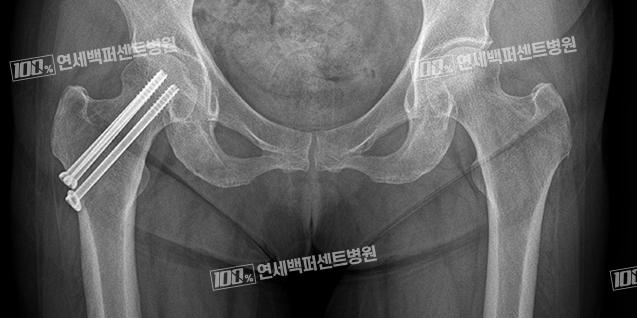

대퇴경부 골절 X-ray

고관절 골절 정복 및 내고정술

전자간 골절, 전위가 없는 급성 대퇴경부골절의 경우에는 골절 부위를 나사와 금속판 또는 골수정을 이용하여 고정하는 수술을 합니다.

전위없는 급성 대퇴경부 골절 수술전

다발성 금속 나사 고정술 후